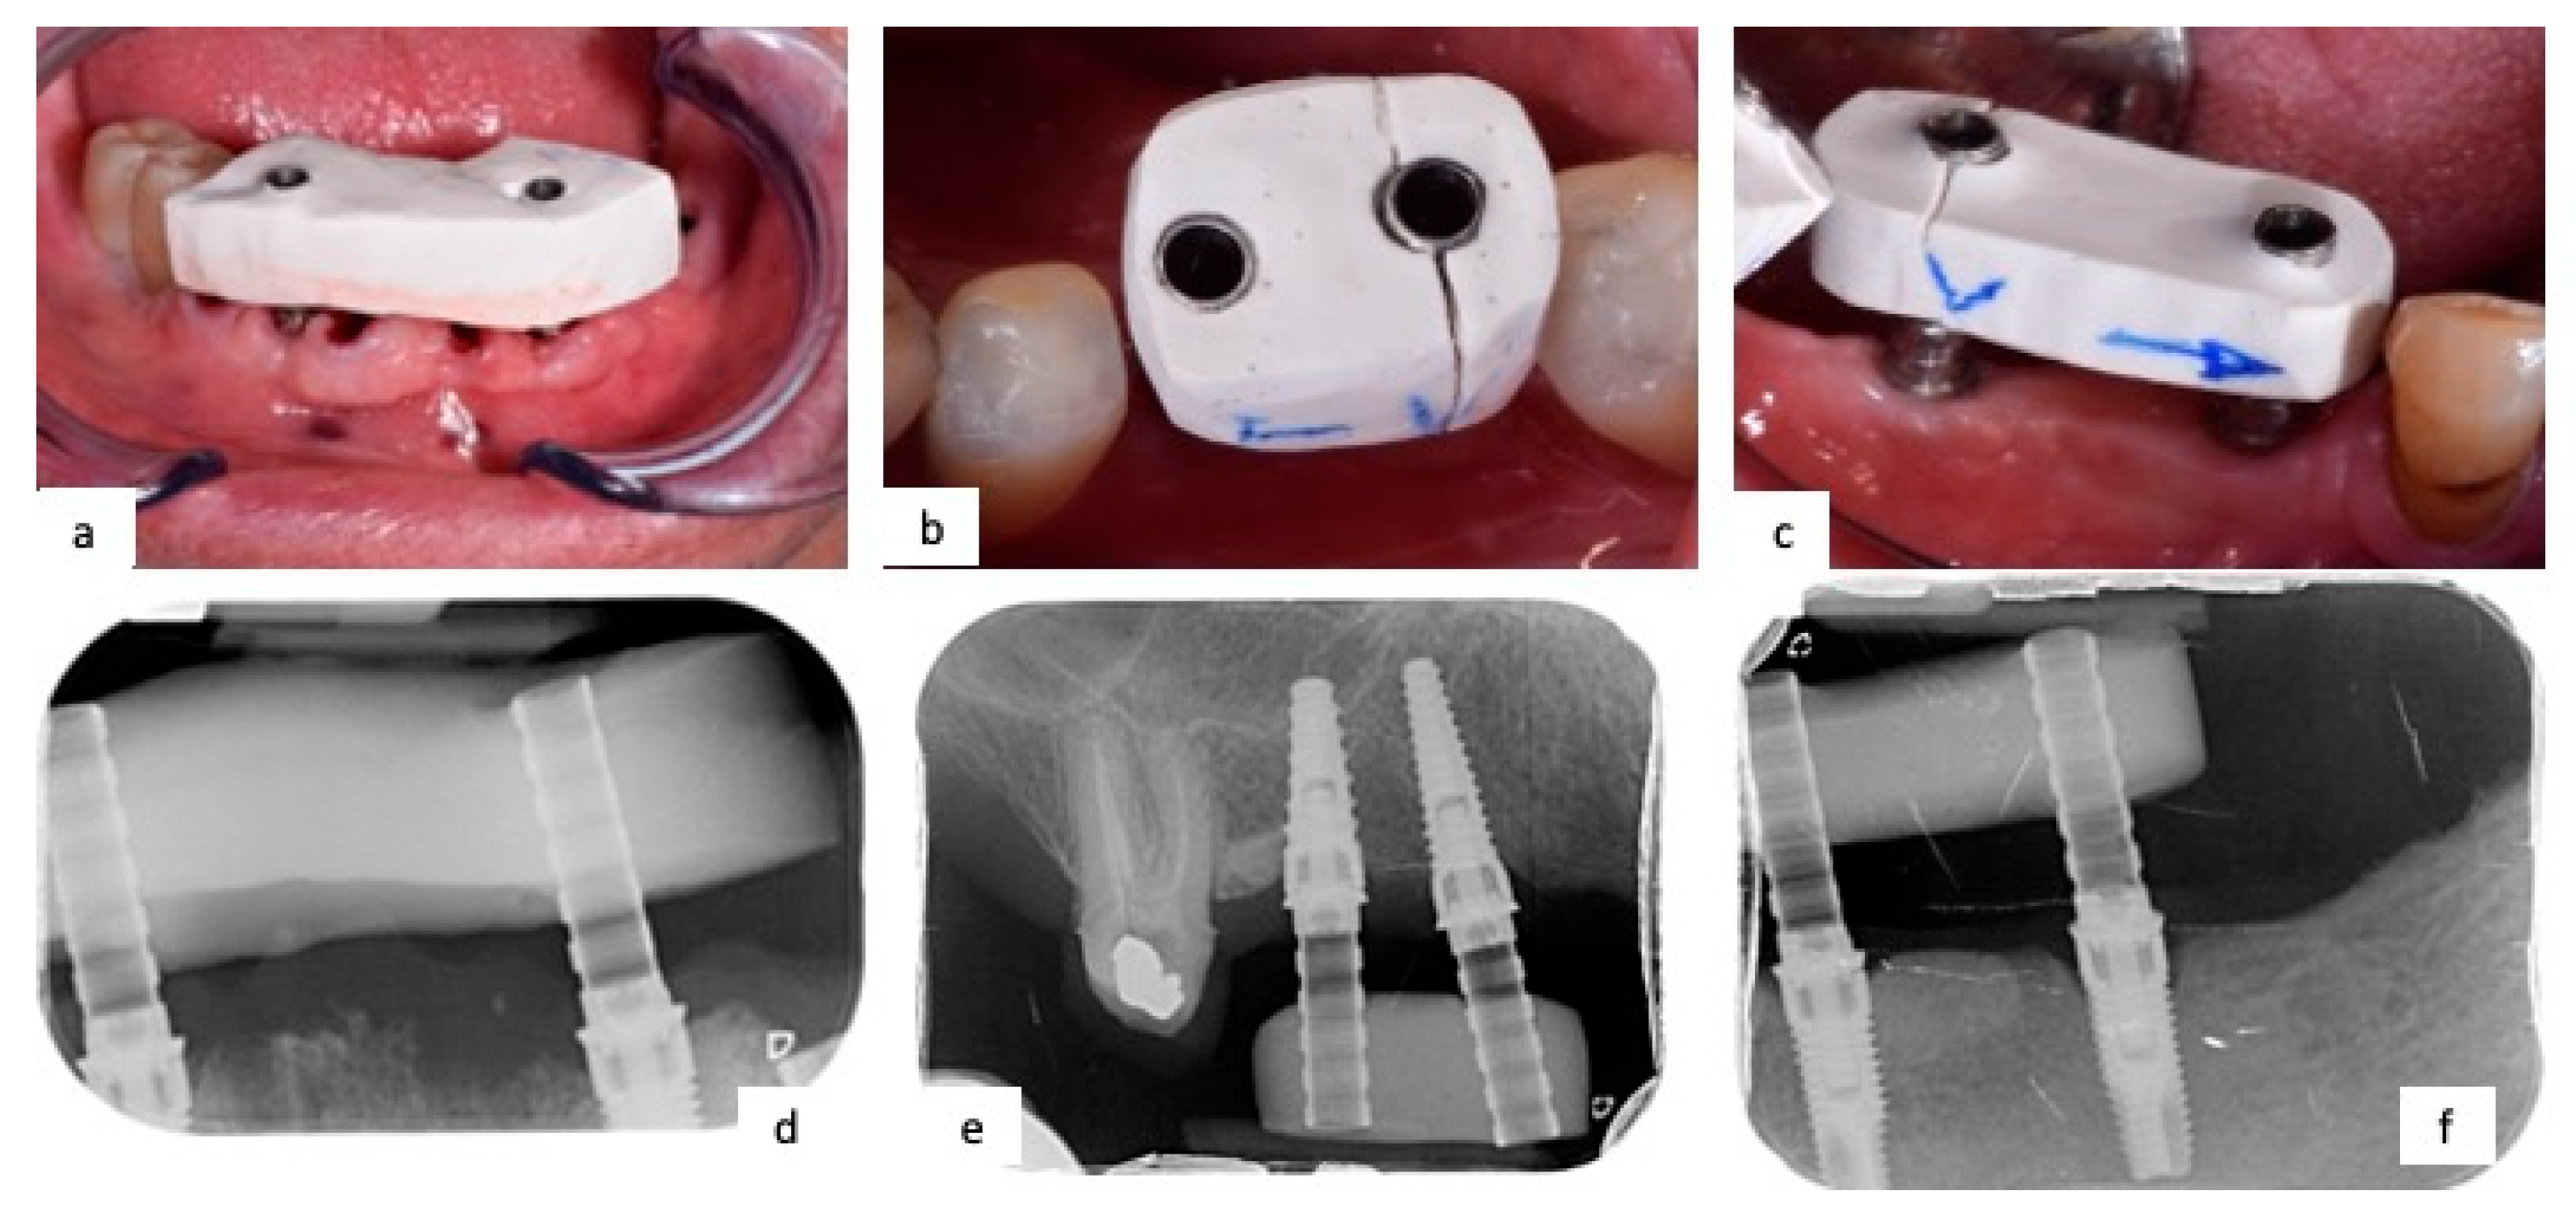

2.2. Workflow and Operating Protocol Description

- Custom tray fabrication after alginate impression, perforated to allow the unscrewing of transfers;

- Removal of the healing screw;

- Positioning of impression transfer coping at 30–35 N;

- Radiological check of correct insertion;

- Splinting of impression transfer coping with Duralay (Reliance Dental, Worth, IL, USA), an autopolymerizing polymethylmethacrylate (PMMA) resin;

- Clinicians took the conventional impression with a polyether (Impregum, 3M ESPE, Dental Products, St. Paul, MN, USA);

- After 6 min, impression transfer copings were unscrewed, and the custom impression tray was removed from the patients;

- Assessment of definitive impression taken;

- Extra-hard plaster cast was made with 4th-type gypsum (Fujirock Ep Classic, GC Corporation, Tokyo, Japan);

- Plaster cast digitalization using 3Shape D500 (Copenhagen, Denmark) laboratory scanner.

- Vivadent Optragate (Schaan, Liechtenstein) retractor was positioned;

- Healing screws were replaced by PEEK scanbodies;

- Optical impression was taken with Carestream 3600 (Rochester, New York, NY, USA);

- STL file was generated on CAD station and the digital cast was reconstructed.

2.4. Clinical Cases